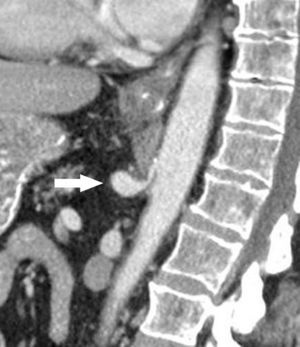

La imagen radiológica que define al signo del moño y la mantilla en el síndrome del ligamento arcuato mediano del diafragma consiste en la visualización, en un mismo plano axial, del tronco celíaco comprimido y deformado entre la aorta abdominal ubicada dorsalmente y el ligamento arcuato mediano localizado ventralmente, el cual rodea prácticamente a los otros dos (fig. 3). Estos hallazgos asemejan una cabeza (aorta) tocada con un moño (origen del tronco celíaco) y cubierta por un paño (ligamento arcuato mediano). Esta analogía es el motivo de su nombre (fig. 4).

Signo del moño y la mantilla en el síndrome del ligamento arcuato mediano del diafragma: corte tomográfico convencional en plano axial del mismo paciente donde se aprecia el tronco celíaco comprimido y deformado entre la aorta abdominal ubicada dorsalmente y el ligamento arcuato mediano localizado ventralmente (flecha). Este último rodea prácticamente a los otros. (Tomado de Soliva Martínez D, Fernández Iglesias P, Belda González I, Martínez Yunta JA, Hernández Muñoz L, Blanco López ME. Hallazgos poco conocidos en el síndrome del ligamento arcuato mediano. 10.1594/seram2014/S-0407).